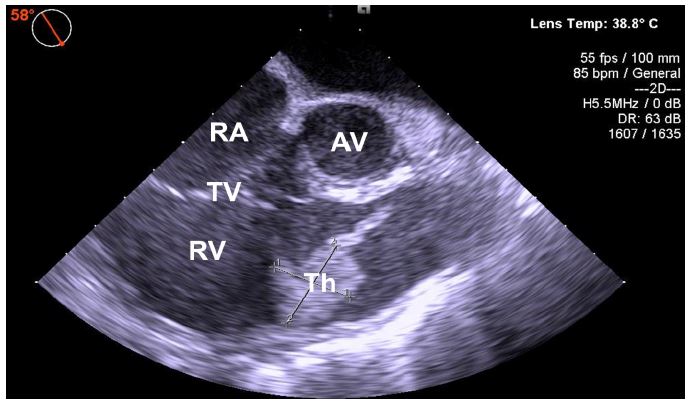

Figure 2: Transesophageal echocardiography image with a floating thrombus in the right atrium crossing into the right ventricle. Midesophageal RV inflow-outflow view at 58° showing the right ventricular portion of the clot of at least 2.30 × 1.95 cm. AV: Aortic Valve; RV: Right Ventricle; Th: thrombus; TR: Tricuspid Regurgitation; TV: Tricuspid Valve.